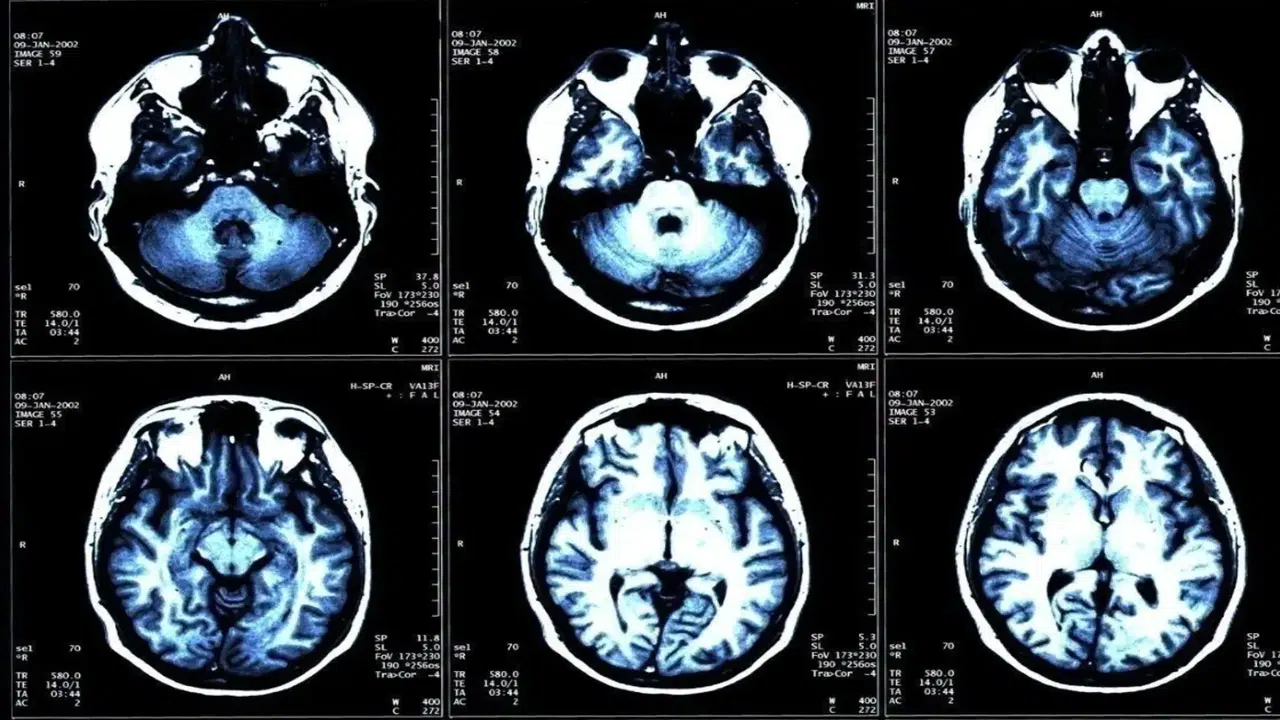

İyot, insan vücudunun sağlıklı işleyişi için hayati önem taşıyan elementlerden biri olarak biliniyor. Tiroid hormonlarının üretiminde temel rol oynayan bu madde, özellikle çocukların büyüme süreci ve beyin gelişimi açısından büyük önem taşıyor. Uzmanlara göre, iyot eksikliği yalnızca fiziksel gelişimi değil, aynı zamanda zihinsel performansı da doğrudan etkiliyor. 21 Ekim Küresel İyot Eksikliği Bozukluklarını Önleme Günü kapsamında açıklamalarda bulunan Endokrinoloji ve Metabolizma Hastalıkları Uzmanı Prof. Dr. Mehmet Fatih Kılıçlı, “Toplumda yeterli iyot alımı sağlıklı nesillerin yetişmesi için kritik bir gerekliliktir” diyerek önemli bir uyarıda bulundu.

Dünya genelinde önlenebilir zeka geriliğinin en sık nedenlerinden biri olarak kabul edilen iyot eksikliği, gelişmekte olan ülkelerde ciddi bir halk sağlığı sorunu olarak görülüyor. Uzmanlara göre bu durum, özellikle kırsal bölgelerde ve iyotlu tuz kullanımının yeterli olmadığı toplumlarda daha yaygın şekilde görülüyor.

Prof. Dr. Kılıçlı’ya göre iyot eksikliği, en çok gebelik döneminde tehlike yaratıyor. Anne adaylarının yeterli iyot alamaması durumunda bebekte kalıcı zeka geriliği, gelişim bozuklukları, ölü doğum ve düşük riski ortaya çıkabiliyor. Ayrıca doğum sonrası dönemde de bebeklerde guatr ve tiroid hormon eksiklikleri gözlenebiliyor. Uzmanlar, gebelik süresince iyot alımının düzenli takip edilmesi gerektiğini, bu dönemdeki eksikliğin hem annenin hem de bebeğin yaşam boyu sağlığını etkileyebileceğini belirtiyor.

Büyüme çağındaki çocuklarda da benzer şekilde iyot yetersizliği gelişim geriliğine, dikkat eksikliğine ve öğrenme güçlüğüne neden olabiliyor. Yetişkinlerde ise uzun süreli eksiklik tiroid bezinde büyümeye, nodül oluşumuna ve kalıcı guatr gelişimine yol açabiliyor.